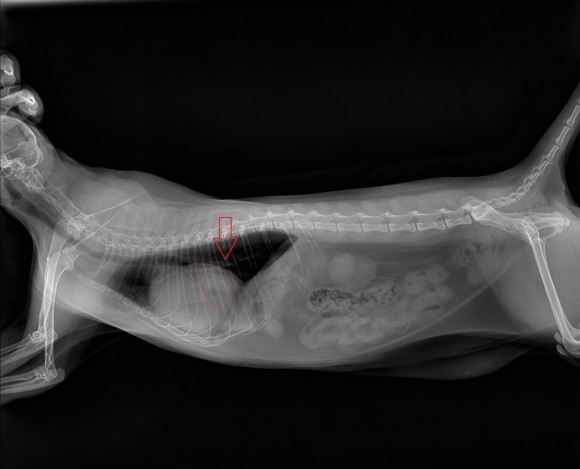

4. 횡격막탈장

횡격막 탈장(고양이), 육안으로 구별이 어렵고 엑스레이로 확인할 수 있는 표면에서는 전혀 깨닫지 못합니다.흉강과 복강을 구분하는 횡격막에 구멍이 있는 경우 횡격막 구멍이 심낭과 연결되어 심낭 안에 간이나 위가 말려드는 경우가 많습니다.

엑스레이 검사로 확인할 수 있습니다.